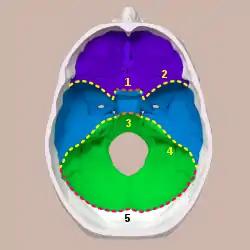

Three cranial fossae and its boundaries. Boundaries | |

A cranial fossa is formed by the floor of the cranial cavity.

There are three distinct cranial fossae:

- Anterior cranial fossa (fossa cranii anterior), housing the projecting frontal lobes of the brain

- Middle cranial fossa (fossa cranii media), separated from the posterior fossa by the clivus and the petrous crest housing the temporal lobe

- Posterior cranial fossa (fossa cranii posterior), between the foramen magnum and tentorium cerebelli, containing the brainstem and cerebellum